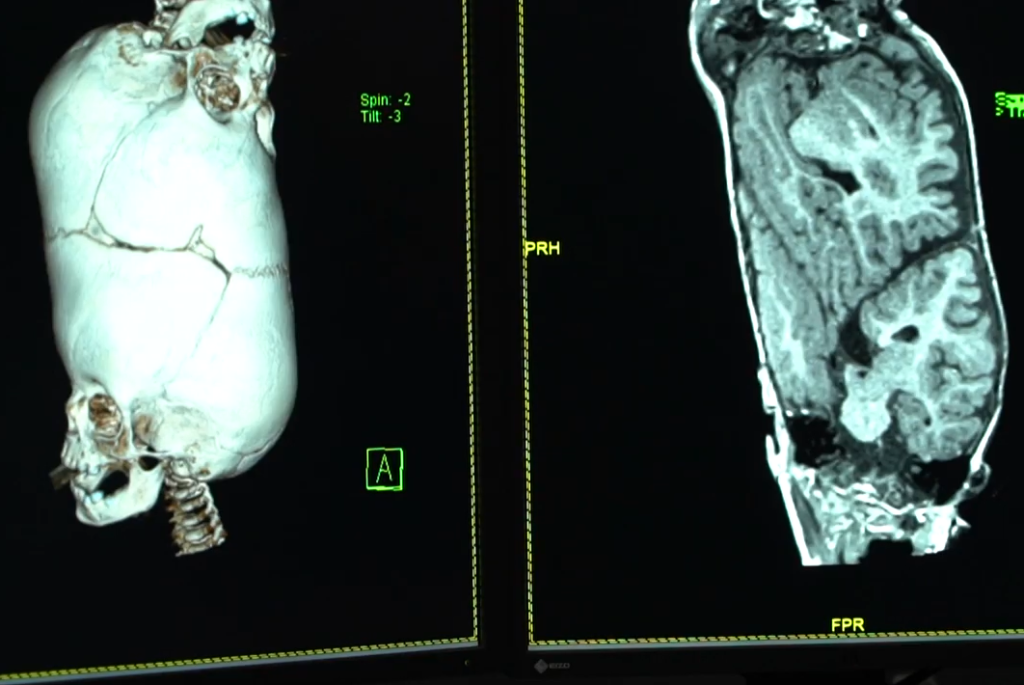

10. Changing One Skull Into Two Skulls

It was a challenging task to create two skulls from a tubular skull. Plus, they needed more skin to cover the skulls.